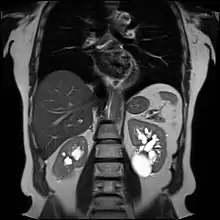

![]() | |

| Renal cyst of the left kidney (hyperintense area) as shown on MRI. | |

Advanced polycystic kidney disease with multiple cysts.[12]